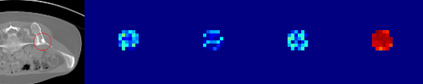

Evaluating lesion progression and treatment response via longitudinal lesion tracking plays a critical role in clinical practice. Automated approaches for this task are motivated by prohibitive labor costs and time consumption when lesion matching is done manually. Previous methods typically lack the integration of local and global information. In this work, we propose a transformer-based approach, termed Transformer Lesion Tracker (TLT). Specifically, we design a Cross Attention-based Transformer (CAT) to capture and combine both global and local information to enhance feature extraction. We also develop a Registration-based Anatomical Attention Module (RAAM) to introduce anatomical information to CAT so that it can focus on useful feature knowledge. A Sparse Selection Strategy (SSS) is presented for selecting features and reducing memory footprint in Transformer training. In addition, we use a global regression to further improve model performance. We conduct experiments on a public dataset to show the superiority of our method and find that our model performance has improved the average Euclidean center error by at least 14.3% (6mm vs. 7mm) compared with the state-of-the-art (SOTA). Code is available at https://github.com/TangWen920812/TLT.